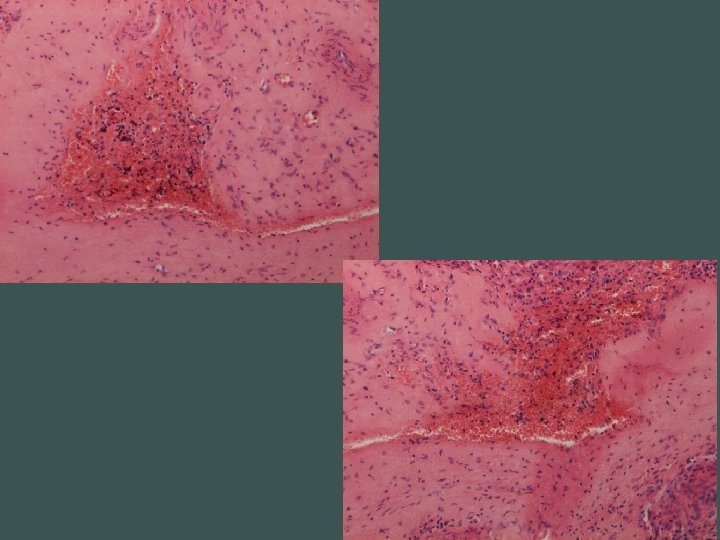

Segmentálna atrofia pečene • zriedkavý pseudotumor • častejšie u žien, unifokálny • najčastejší príznak bolesť horného pravého kvadrantu • prevažne subkapsulárne • 1, 8 - 10 cm • abnormálne hrubostenné cievy (len intralezionálne), často trombotizované, rekanalizované • biliárne cysty

Abnormálne cievy • vyvolávajúci impulz ischémia?

Dif. dg. • amyloidóza • epiteloidný hemangioendotelióm • cancer- asociovaná elastóza (cholangio CA, MTS adeno CA)